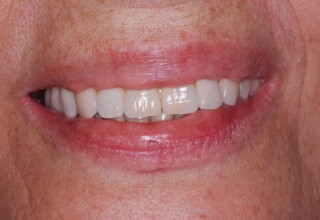

Porcelain Veneers

The best way to solve esthetic problems of the anterior teeth. They combine very little tooth grinding with very high esthetic performance. In the following extensive case anterior teeth presented with: old restorations, staining, poor shape, length and tooth –gingiva ratio. Meticulous diagnostic waxing was performed on study casts and temporary veneers were manufactured. Temporary veneers were used intraorally to evaluate the incorporated changes and to further modify and adjust were needed. When esthetics and function were approved by the patient and were satisfying for the operator the temporaries were used as a guide for the final porcelain veneers. The five final veneers on the upper anterior teeth restored the smile of the patient to almost perfection.

Initial appearance

Final appearance